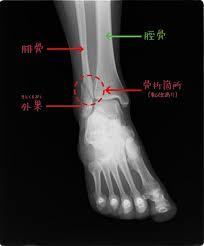

というわけで、本日、ようやく整形外科を受診し、レントゲンを撮ってもらったところ、

見事に左下腿の腓骨(ひこつ)を骨折しており、即“ギブス”生活となりました。

骨折部の転位がなかったのが不幸中の幸い、入院・手術は免(まぬが)れました。

[画像は右腓骨骨折の場合の資料画像]